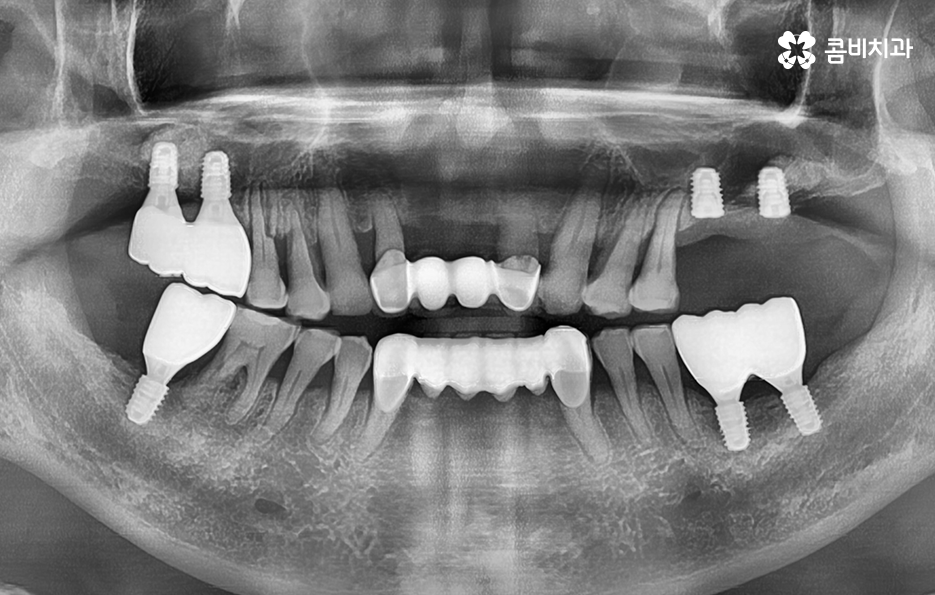

50대에 관리가 잘 안되던 치주질환은 결국 60대에 이르러 한꺼번에 여러 치아를 상실하게 되고 그에 따라 임플란트도 여러개를 식립해야 하는 사례가 많다는 점을 주목하실 필요가 있는데요

50대에는 치주염, 충치, 외상과 같은 사유로 인해 치아를 하나 둘씩 잃게 되는 사례가 많으며 치아 상실 후에 즉시 임플란트 치료를 받지 않는다면 잇몸과 턱뼈는 서서히 퇴축되고 약화되며 치열이 망가질 수 있는 우려와 교합이 제대로 물리지 않는 불균형이 나타날 수 있어요

50대는 앞으로의 기대수명이 길기 때문에 치아 상실 후 방치하기 보다는 꼭 임플란트 치료를 하는 것이 합리적이며 치아 상실 후에는 골 흡수가 진행되지만 임플란트를 하면 잇몸 뼈를 보존할 수 있다는 점에서도 앞으로의 노후대비에 있어서도 임플란트는 중요한 시술이 될 수 있어요

치료를 건강하게 받는 것과 동시에 앞으로의 기대수명 만큼이나 임플란트 수명 역시도 건강하게 보존해야 하며 임플란트는 사후관리에 따라서 수명의 개인차가 크다는 점을 염두하셔서 오래 믿고 찾을 수 있는 치과를 철저히 따져보시길 바라고 있어요